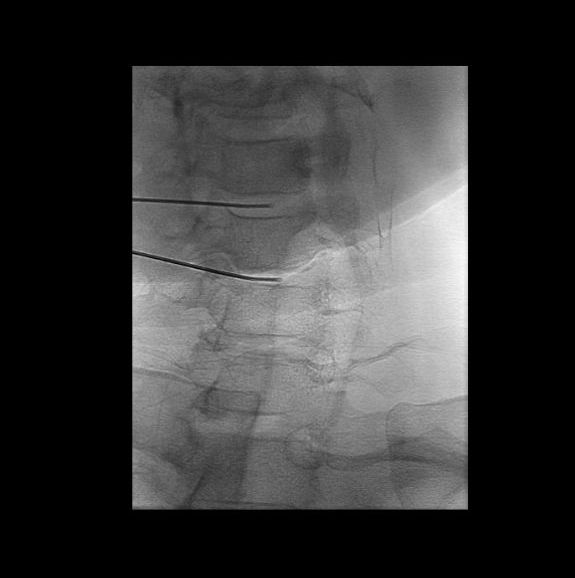

Η δισκοπλαστική εφαρμόζεται με τον ασθενή υπό τοπική αναισθησία, ελαφρά ενδοφλέβια καταστολή και ακτινοσκοπική καθοδήγηση. Μια ειδική λεπτή βελόνα τοποθετείται εντός του πυρήνα του εκφυλισμένου και επώδυνου δίσκου. Δια μέσω της βελόνας εισάγεται ηλεκτρόδιο το οποίο συνδέεται με γεννήτρια ραδιοσυχνοτήτων, η οποία παράγει και εφαρμόζει στον πυρήνα του δίσκου, δια μέσω του ηλεκτροδίου, ηλεκτρομαγνητικό πεδίο, το οποίο απευαισθητοποιεί τους υποδοχείς πόνου του εκφυλισμένου δίσκου και μειώνει τη φλεγμονή, ενισχύοντας τη δράση του ανοσοποιητικού συστήματος.

Στη συνέχεια αποσύρεται το ηλεκτρόδιο και γίνεται έγχυση του Discogel εντός του πυρήνα του δίσκου, δια μέσω της ίδιας βελόνας. Το Discogel έχει την ιδιότητα να προσροφά νερό και να συνθέτει έναν ανανεωμένο πυρήνα, καθώς και να κλείνει τις ρωγμές του περιβλήματος του δίσκου.